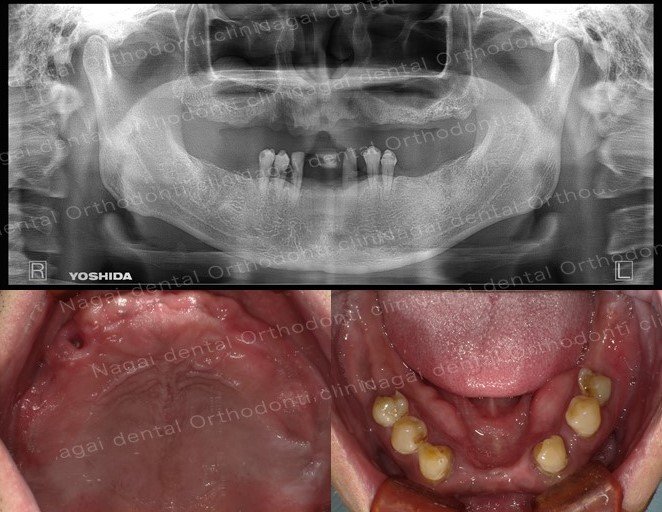

【口腔内の詳細変化】

▲再構築を目的とした治療を行いました

▲欠損していた左上奥歯部分の補綴完了状態

▲支持の安定が期待される治療を行いました

| 治療内容 | 上顎:オールオン4 |

| 年齢/性別 | 30代/男性 |

| 背景 | 多数歯欠損と咬合崩壊を主訴に来院。上顎は骨造成を回避し即日回復を目指したオールオンフォー、下顎は臼歯部インプラントによる再構成を選択しました。チタンフレームとジルコニアで耐久性と審美性を両立。術後は適切な噛み合わせにより咀嚼能率が向上し、機能・審美面ともに満足度の高い日常生活を取り戻されています。 |

| 治療期間 | 約5か月(通院8回) |

| 費用 | 5,384,400円(税込み) |

| リスク/副作用 | インプラント手術は全身状態や持病によっては適応できない場合があります。また、術後の口腔清掃を怠ると、天然歯の歯周病に似たインプラント周囲炎が起こる可能性があるため、定期的なメンテナンスが必要です。 |